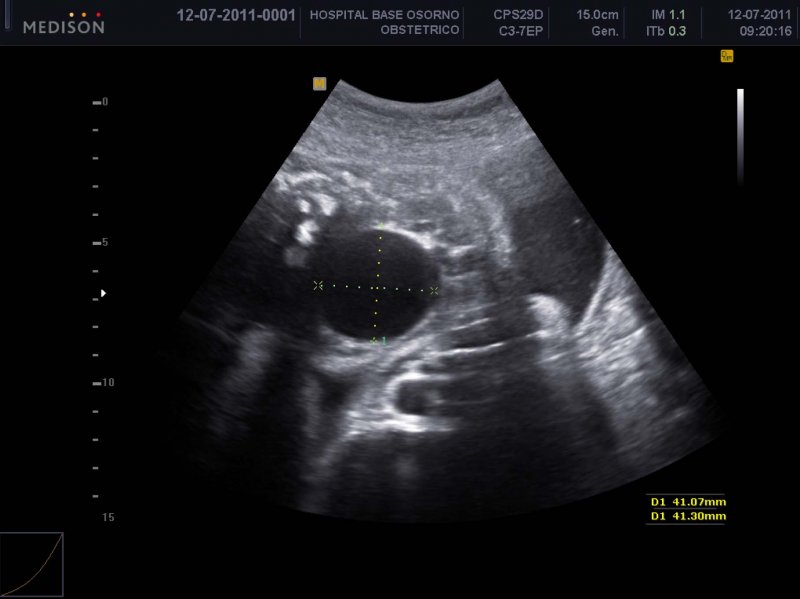

Gestante de 24 años sin patologías asociadas. Durante la ecografía a las 34 semanas se observa una imagen quística intraabdominal de 41 mm de diámetro, con paredes nítidas y contenido anecogénico, en un feto de sexo femenino que crece sobre percentil 90, sin otras alteraciones anatómicas. Se diagnostica quiste ovárico simple (Figura 1). Se mantiene control semanal que demuestra persistencia de la lesión sin variaciónes significativas. A las 41 semanas se realiza cesárea electiva por macrosomía, la que se efectúa sin complicaciones. Recién nacido de sexo femenino, 4735 gramos de peso, 53,5 cm de talla, Apgar 9-10. El examen físico es normal, especificando abdomen blando, depresible e indoloro, sin tumor a la palpación. Por el diagnóstico prenatal de QO es evaluada por ginecóloga infantil al segundo día de vida. Al examen presenta abdomen blando y sin evidencia de tumor, llanto solo a la palpación profunda. Se confirma genitales externos sanos con vagina permeable. Mediante ecografía se ratifica presencia de quiste de 39 mm de diámetro en flanco y fosa iliaca izquierda, de pared fina, con vascularización periférica al Doppler y un marcado nivel de liquido-detritus (Figura 2). Se diagnostica QO complicado, altamente probable por torsión. Es evaluada por cirujano infantil descartándose otras causas. En conjunto se realiza laparoscopia a las 7 horas de establecido el diagnóstico. En esta se encuentra quiste de 4 cm de diámetro, superficie lisa de coloración café que compromete completamente al ovario derecho. Está torcido 2 veces sobre su pedículo, desplazado hacia cuadrante inferior izquierdo y no compromete la trompa. Se punciona obteniendo 25 cc de líquido hemorrágico, se liberan adherencias laxas epiploicas y destuerce el ovario. Luego se realiza destechamiento del quiste y se explora la pared interna confirmando superficie lisa. La cirugía termina sin complicaciones y la paciente presenta una adecuada recuperación postoperatoria. Se realiza control ecográfico a los 15 y 90 días confirmándose ausencia de recurrencia. El estudio citológico del contenido del quiste fue negativo para células neoplásicas malignas.

El diagnóstico es principalmente ecográfico y se basa en la presencia de 4 criterios (10): sexo femenino, estructura quística de contorno regular fuera de la línea media, tracto urinario y gastrointestinal de apariencia normal. La ecografía también nos permite establecer si el QO está complicado. Los no complicados son de pared fina y de contenido anecogénico, los complicados por torsión o hemorragia intraquística se presentan con contenido hiperecogénico o tabiques finos o pared fina hiperecogénica o con nivel líquido/detrito en su interior (10). Este último es el signo más característico de torsión, tal como se presentó en nuestra paciente.